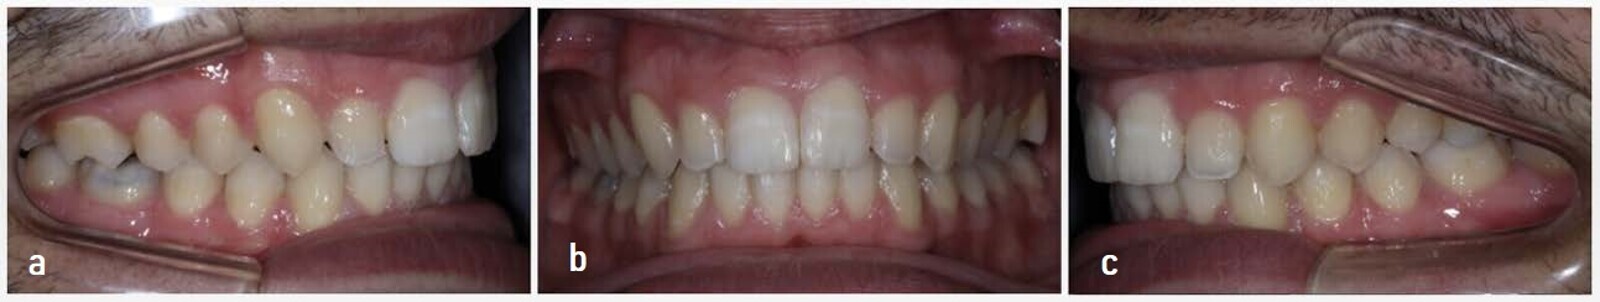

Four years after this case had been completed, the patient came for a review, and both radiographic and photographic records were taken to evaluate any changes that may have occurred over this retention period (Figs. 26–30). Cephalometric analysis was performed again and the results compared with the immediate post-treatment results (Table 2).

Figs. 30a–h: (a–e) Intra-oral and (f–h) extra-oral photographs taken on 23 June 2021.